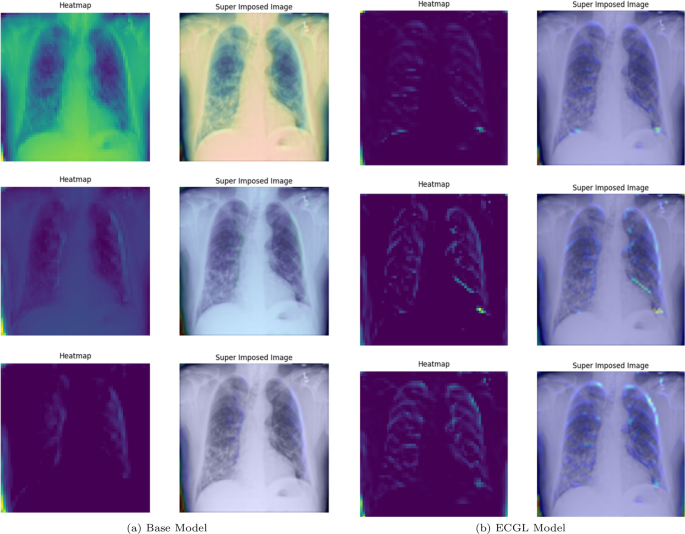

GradCAM Heatmaps and superimposed images of the (a) base model and (b) ECGL model for incorrectly labeled instances. The illustrated heatmaps correspond to GradCAM visualizations for labels 0 (normal), 1 (pneumonia present), and 2 (pneumonia absent, abnormalities exist), arranged from top to bottom, respectively. (a) base Model. (b) ECGL model

GradCAM Heatmaps (left column) and Superimposed images (right column) of the (a) Base model and (b) ECGL model for incorrectly labeled instances. The illustrated heatmaps correspond to GradCAM visualizations for labels 0 (normal), 1 (pneumonia present), and 2 (pneumonia absent, abnormalities exist), arranged from top to bottom, respectively

Moreover, in spite of both models’ similar performance illustrated in Fig. 5(a) and 5(b), the GradCAM visualizations clearly demonstrate noticeable differences. The Base model resulted in a more scattered visualization that may not correspond to the actual pathology. This indicates that the Base model’s prediction can be based on irrelevant features and not focused on the main required regions. The proposedECGL model, on the other hand, highlighted regions that are more relevant to the considered medical condition, suggesting that the constraints have helped the model focus on more meaningful features.

Unlike the Based model, the ECGL model’s heatmap for the incorrect prediction is more localized, highlighting a specific region in the lung. The overlay shows that there is indeed an abnormality in this area, but it could have been insufficient to confidently classify the image, which resulted in an incorrect final prediction. While such false predictions highlight the complexity of the task, the findings suggest that adding the constraints and guiding the model with domain-specific explanations through proposed ECGL can enhance the model’s explainability even when overall accuracy remains quite the same. Using such explainability, the experts can better identify the model’s deficiencies and limitations, leading to efficient mitigation of them.